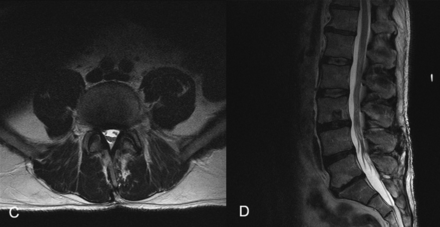

The images below are from just three of the many published case studies showing severe bulging discs in the neck and lower back that the nervous system was able to heal naturally:

Case Study 3: